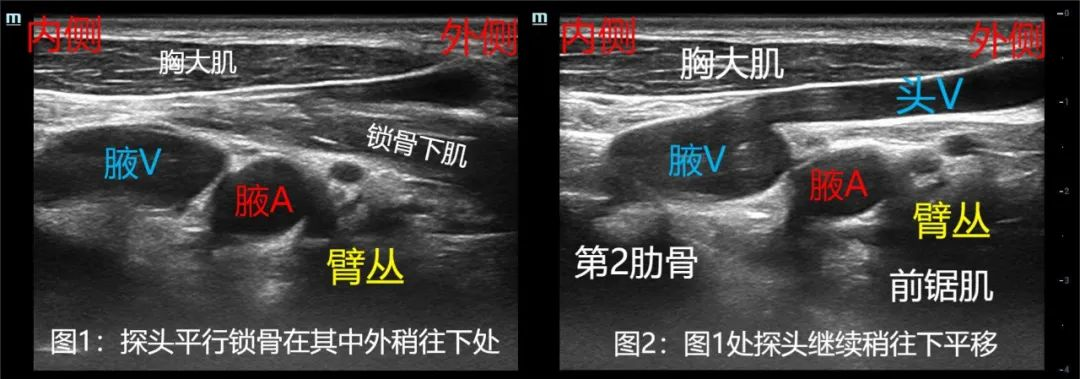

精准之道 | 图解超声引导神经阻滞(2)--肋锁间隙入路“臂丛阻滞”(3束)方法及特点